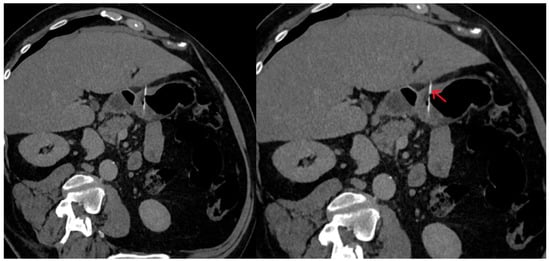

2. Case Report